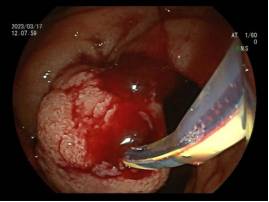

3.早期消化道肿瘤ESD技术

内镜下粘膜剥离术(ESD),具有超级微创、安全性高、住院时间短及费用低等优势,治疗早期胃癌、食管癌、大肠癌等病变,5年生存率超90%。

直肠巨大绒毛状腺瘤 内镜下粘膜剥离过程

粘膜剥离术后创面 剥离的巨大腺瘤